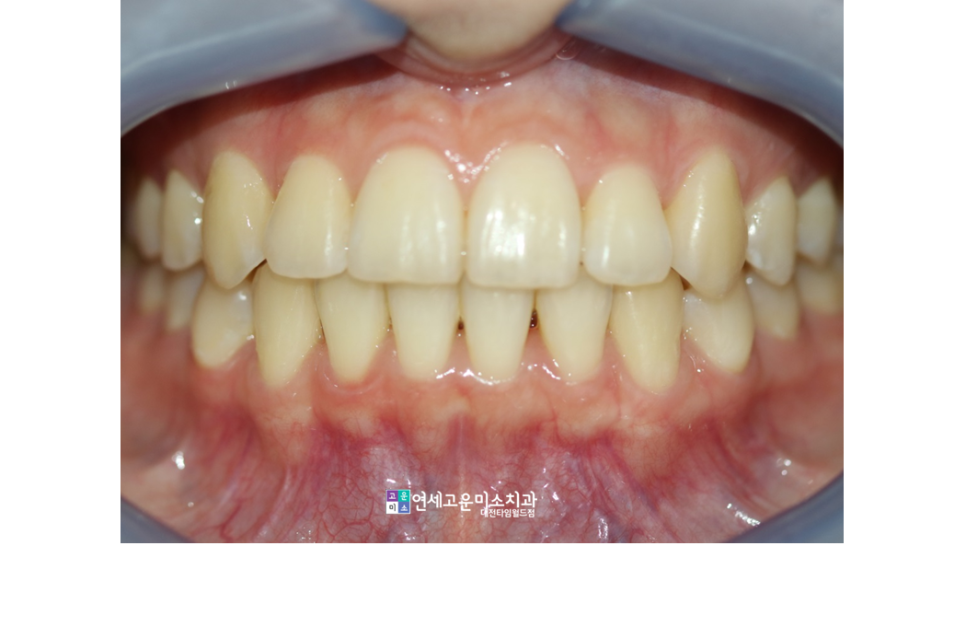

치료가 끝난 이후의 모습입니다.

완치에 이르기까지는 대략

2년 정도가 소요되었습니다

(2021. 3. ~ 2023. 1.)

단순하게 앞니만 배열하기보다는

전반적인 부정교합을 어떻게

정상적으로 만들 것인가에 대해

충분히 고민하고 치료해야 합니다.

전후를 비교해보았습니다.

배열이 잘 마무리되었으며

중심선도 정확히 일치시켰습니다.

교정이 끝나고 나서 치아가 아주

건강해 보이는 느낌입니다.

저는 교정 후 이런 모습이 좋습니다^^